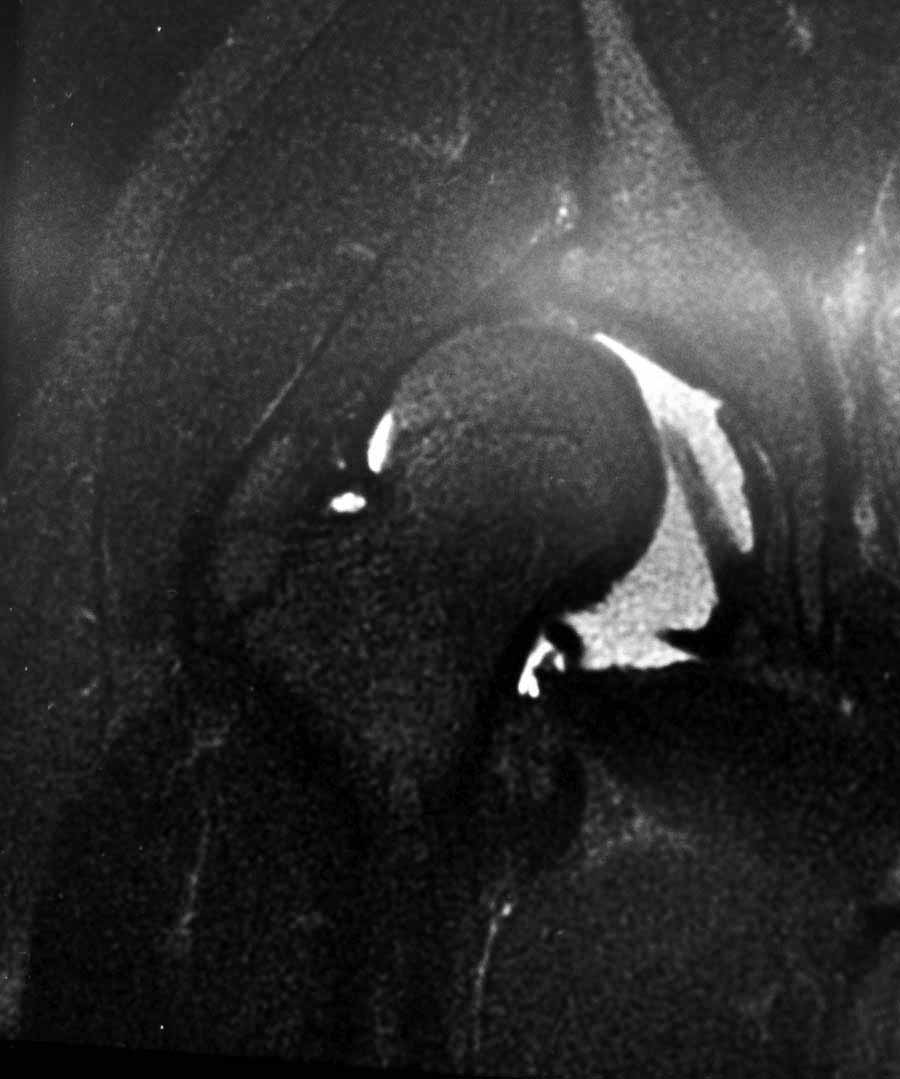

Жалобы на двухсторонние постоянные боли при нагрузке и неустойчивость. Внутренная ротация конечности в суставе более 40 градусов и на рентгенограмме двухсторонний подвывих головки с нарушением линии Шентона, а на боковом снимке с минусовым покрытием головки. МРТ - удлиненная связка и импинджмент (бугор) в шейке.

Первым этапом сделана подготовка к ротационной межвертельной остеотомии, затем капсулотомия с удалением импинджмента и периацетабулярная остеотомия с 40 градусной экстензией и операция закончена 35 градусной наружной ротацией бедра. Запланированный варус не сделан из-за относительно нормального покрытия головки.